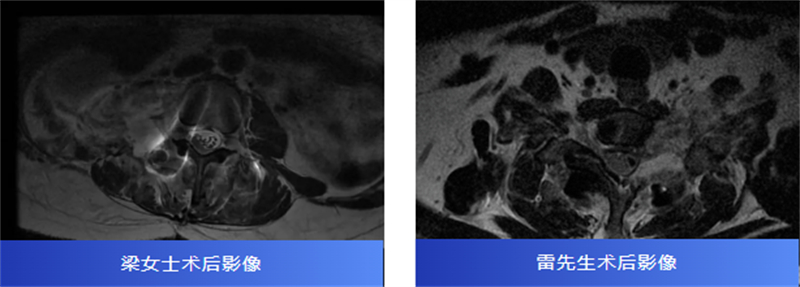

后來,經過腰椎磁共振檢查,才發現原來是椎管內長了一個腫瘤,壓迫著神經,并向外生長,延伸到了右腎附近,情況十分復雜。

兩名患者轉診至柳州市人民醫院后,脊柱外科主任、主任醫師胡巍博士迅速組織醫學影像科、麻醉科等多學科會診。團隊對腫瘤病變范圍、與神經的毗鄰關系進行周密評估,為每位患者制定個體化手術方案。

術中,在顯微鏡輔助下,醫生精細分離腫瘤與神經組織,小心翼翼解除壓迫,最終切除了腫瘤。病理報告也帶來好消息:兩人均為良性神經鞘瘤。

術后,梁女士的腰腿痛消失了,雷先生的頸肩脹痛也得到了緩解。兩位患者都保住了正常的神經功能,步入康復的新階段。